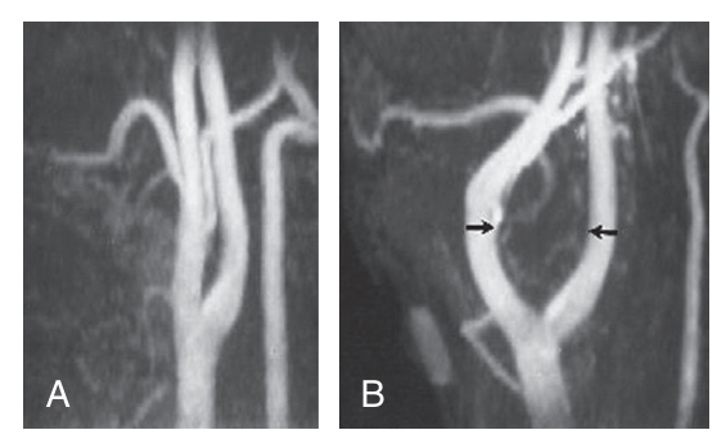

Arteriography-Shows the carotid bifurcation to be splayed open by the mass which is rich in vascularity

What is Lyre sign in CT scan? angiogram - most likely carotid body tumour